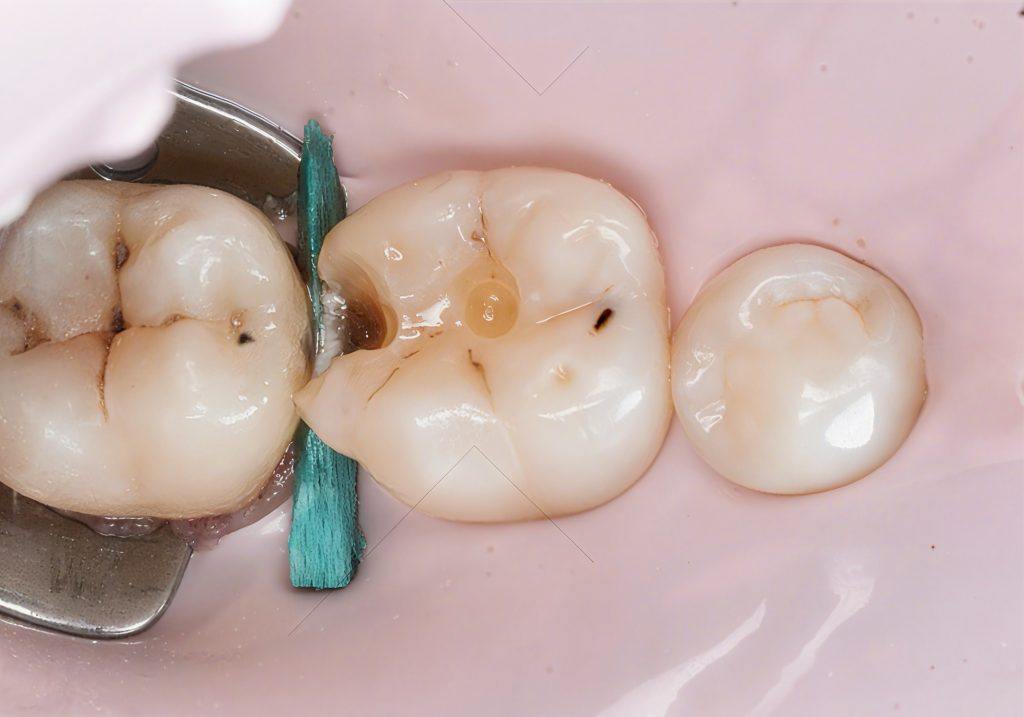

You can clearly see in the photos:

- clean peripheral enamel

- sound dentin base

- a defined proximal box ready for matrix placement

4.3 Matrix Placement & Contact Formation

A sectional matrix with a wooden wedge and separation ring was used.

The key elements:

- matrix positioned flush with the gingival margin

- firm wedge to seal the cervical gap

- ring for slight tooth separation

- ensuring a slight convexity cervically to mimic natural emergence

This combination created the space needed to form a tight, anatomical contact.